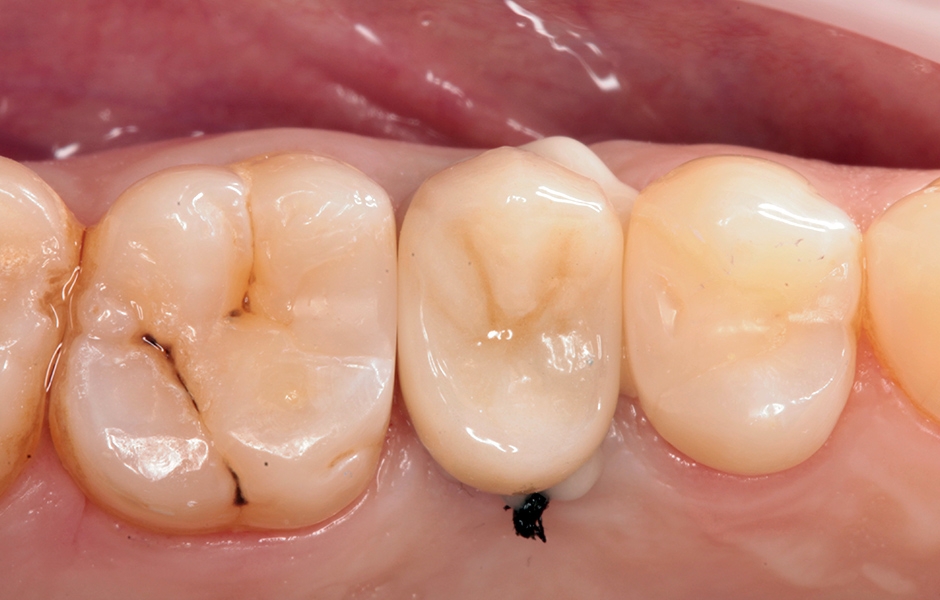

Pacientka sa dostavila na našu kliniku s deštruovaným zubom č. 15 (obr. 1) . Okamžitá implantácia po extrakcii nebola možná, z dôvodu periapikálneho nálezu a nedostatku kostných tkanív potrebných na priamu stabilitu implantátu. Preto sme sa rozhodli daný zub odstrániť a ranu uzavrieť pomocou biomateriálov.

Obr. 1